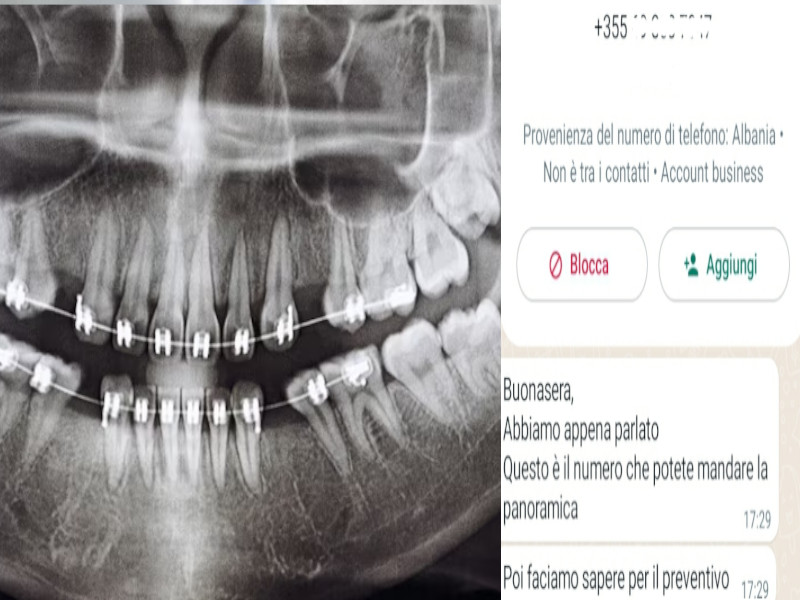

Cure dentali, riparte l’assalto dall’Albania per trovare clienti in Sardegna: “Viaggio e alloggio compreso ma prima la panoramica”

Ritornano alla carica i call center "incollati" a studi dentistici, più o meno noti, con sede nel cuore dei Balcani. ...